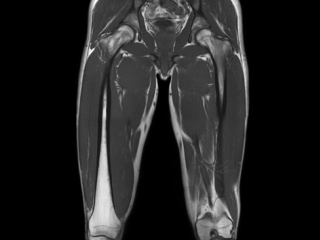

Саркома мягких тканей бедра на МРТ

КТ мягких тканей бедра

Компьютерную томографию бедра проводят при травмах этой области, для оценки состояния сосудистой системы и с целью выявления воспалительных и неопластических процессов. В изучении структуры рыхлых элементов чаще применяют МРТ, которая отличается высокой информативностью и безопасностью. Но в некоторых случаях, например при наличии противопоказаний, назначают мультиспиральную КТ.

КТ с применением контраста визуализирует сеть сосудов, их проходимость, наличие образований в просвете вен и артерий. Благодаря послойным снимкам можно определить характер кровоснабжения области бедра, увидеть локализацию травматических изменений и новообразований.